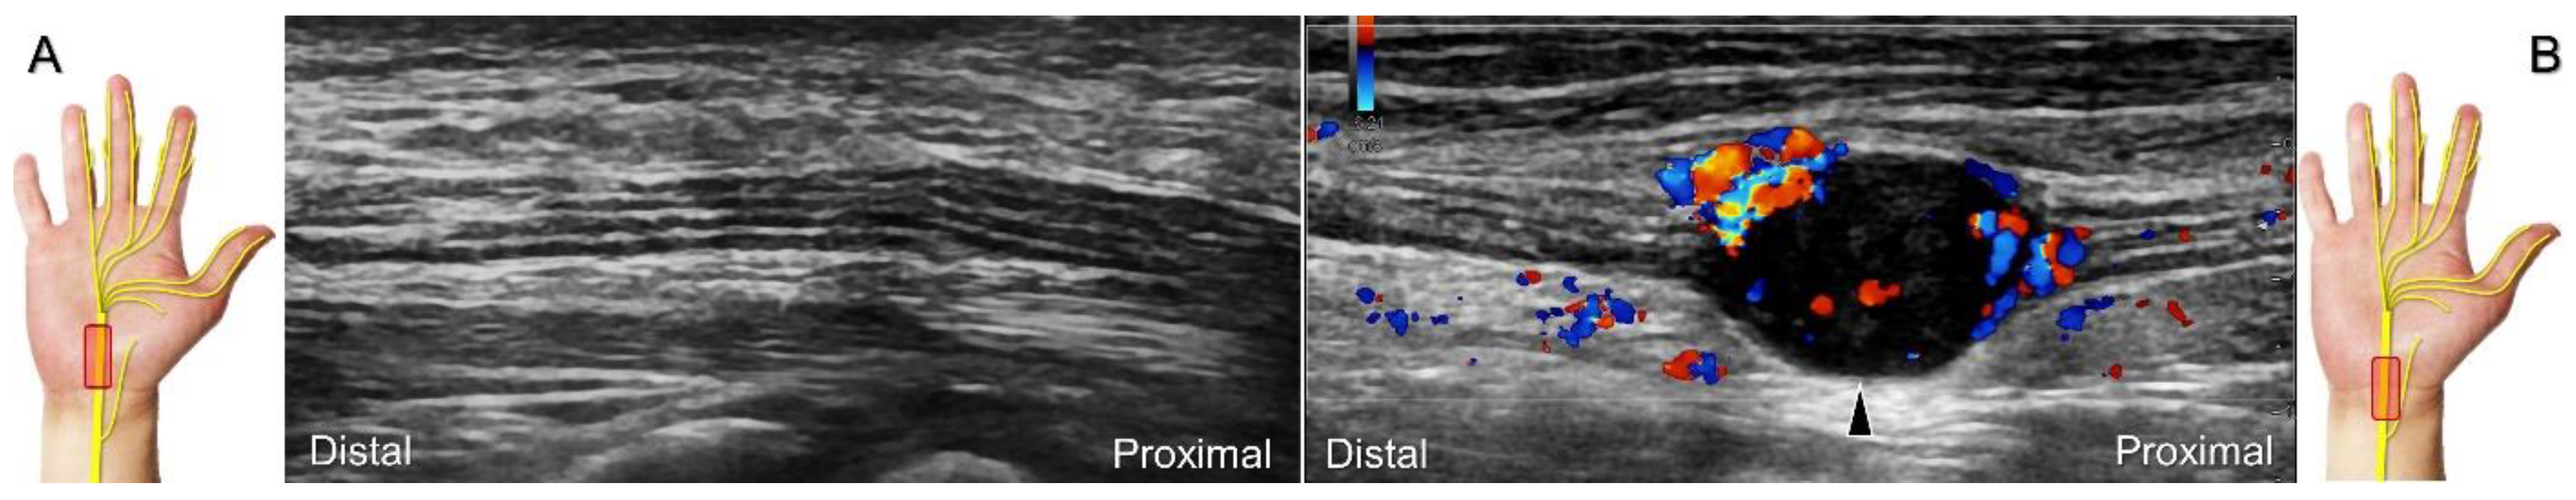

Figure 5. Comparative ultrasonography (long-axis view) between healthy (A) vs. affected (B) sides shows a schwannoma (black arrowhead) with increased intraneural vascularity.